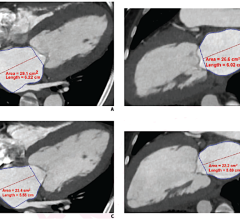

The first award exhibit, was entitled, A Truly Clientless AJAX-based 3D Image Viewer for MIRC Based on an IHE-TCE-Compliant 3D Client-Server Solution. This winning exhibit featured the AquariusWEB viewer, which was embedded seamlessly into the RSNA Medical Imaging Resource Center (MIRC) project for managing image-based teaching files for educational and research purposes.

The second award exhibit was entitled, Novel Uses of the Nintendo Wii Remote in the Navigation of Multidetector CT Datasets. In this instance, the Wii-mote was used as an alternative to traditional mouse-based input, to manipulate and review volumetric CT data. The flexibility of holding the Wii-mote in the hand removes the structured boundaries of a normal mouse and allows the user to remove the learning curve sometimes needed to manipulate a PC mouse.

Another exhibit utilized a “Multi-Touch” display to navigate volumetric CT and MR datasets. This technology allows users to manipulate data directly with their fingers through a touch screen and promises to remove the learning curve and constraints of a traditional mouse or trackball, icons and pull down menus.